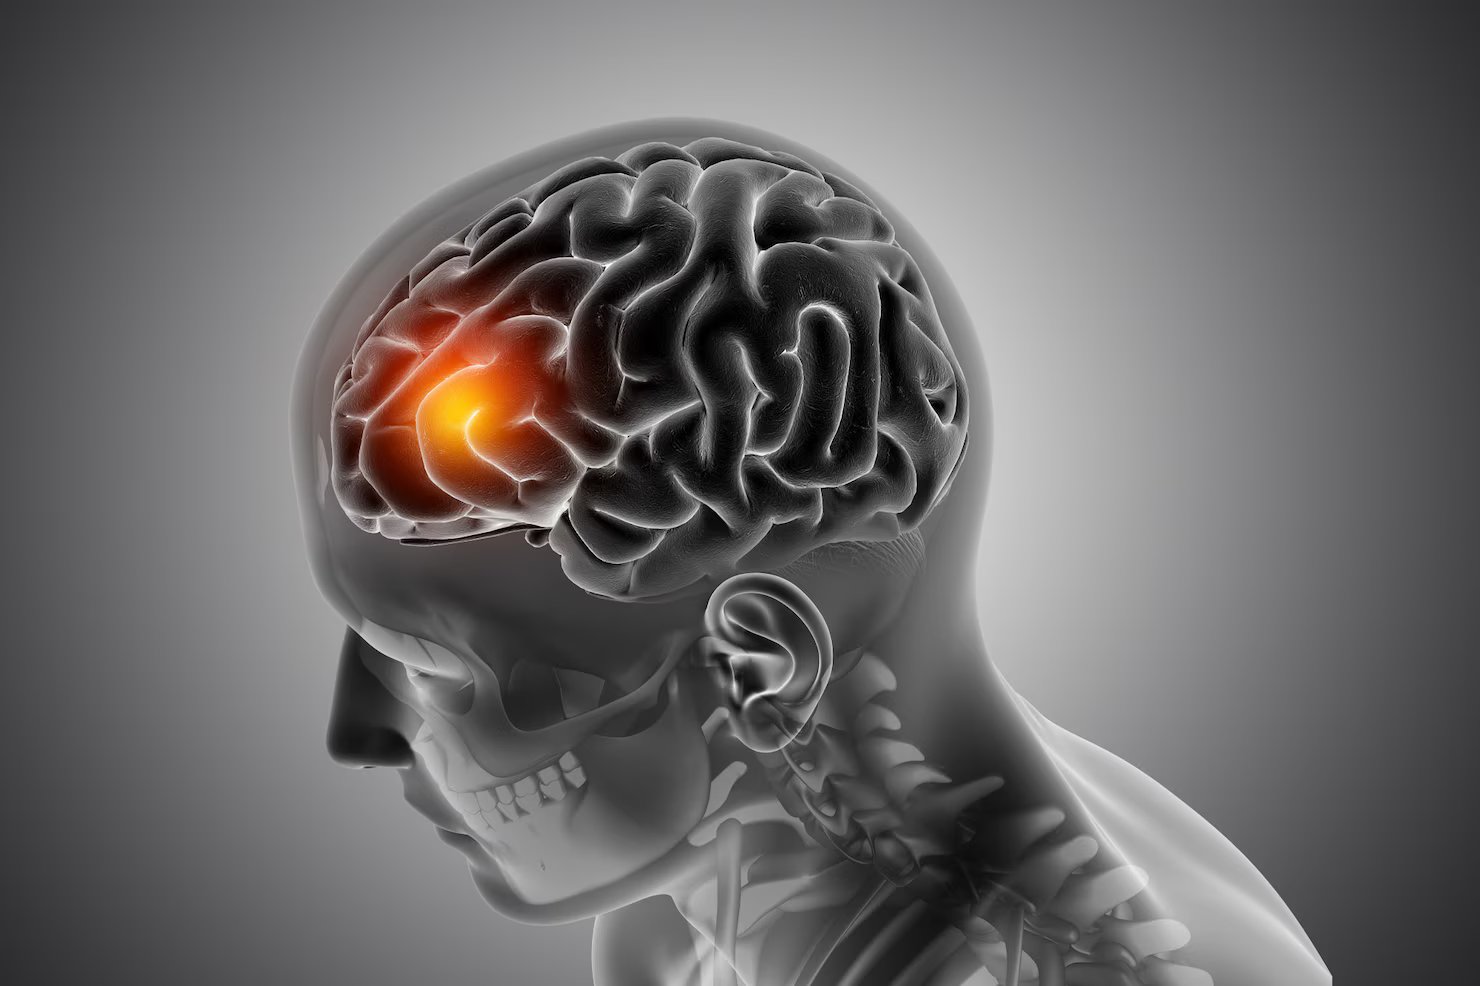

Specialized treatment for brain, spine, and nervous system disorders ensuring optimal neurological health.